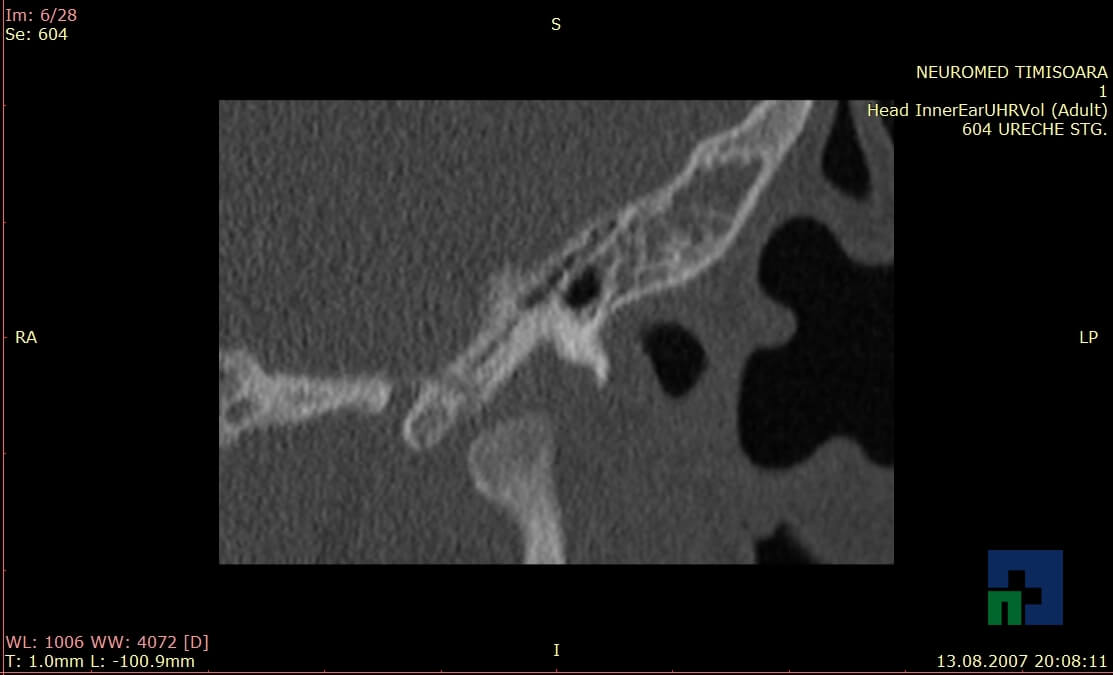

- Diagnosticul traumatismelor de bază de craniu

- Diagnosticul fistulei LCR